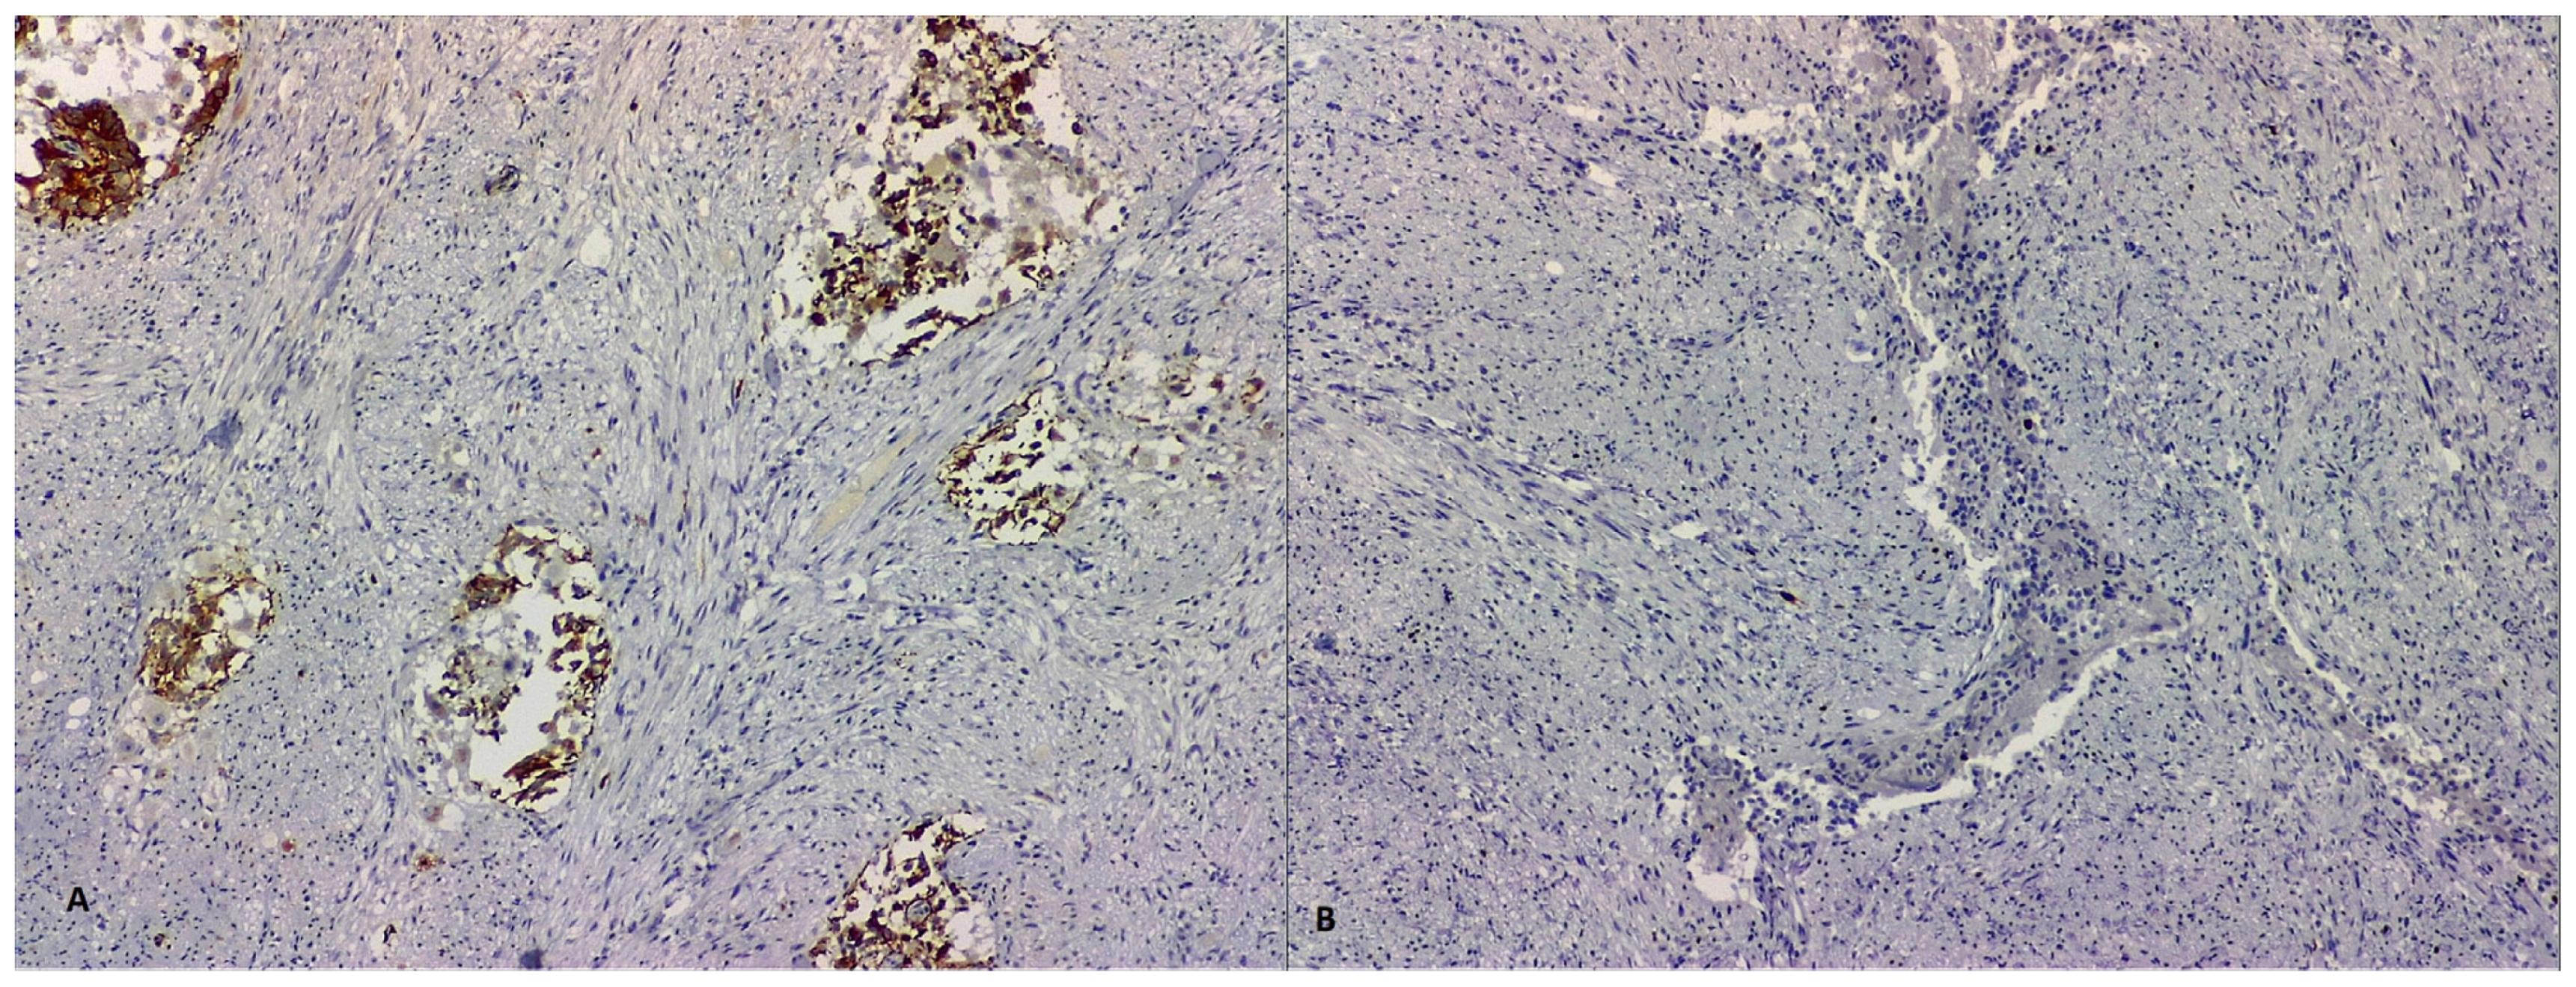

2. Case Report 1

3. Case Report 2

4. Case Report 3